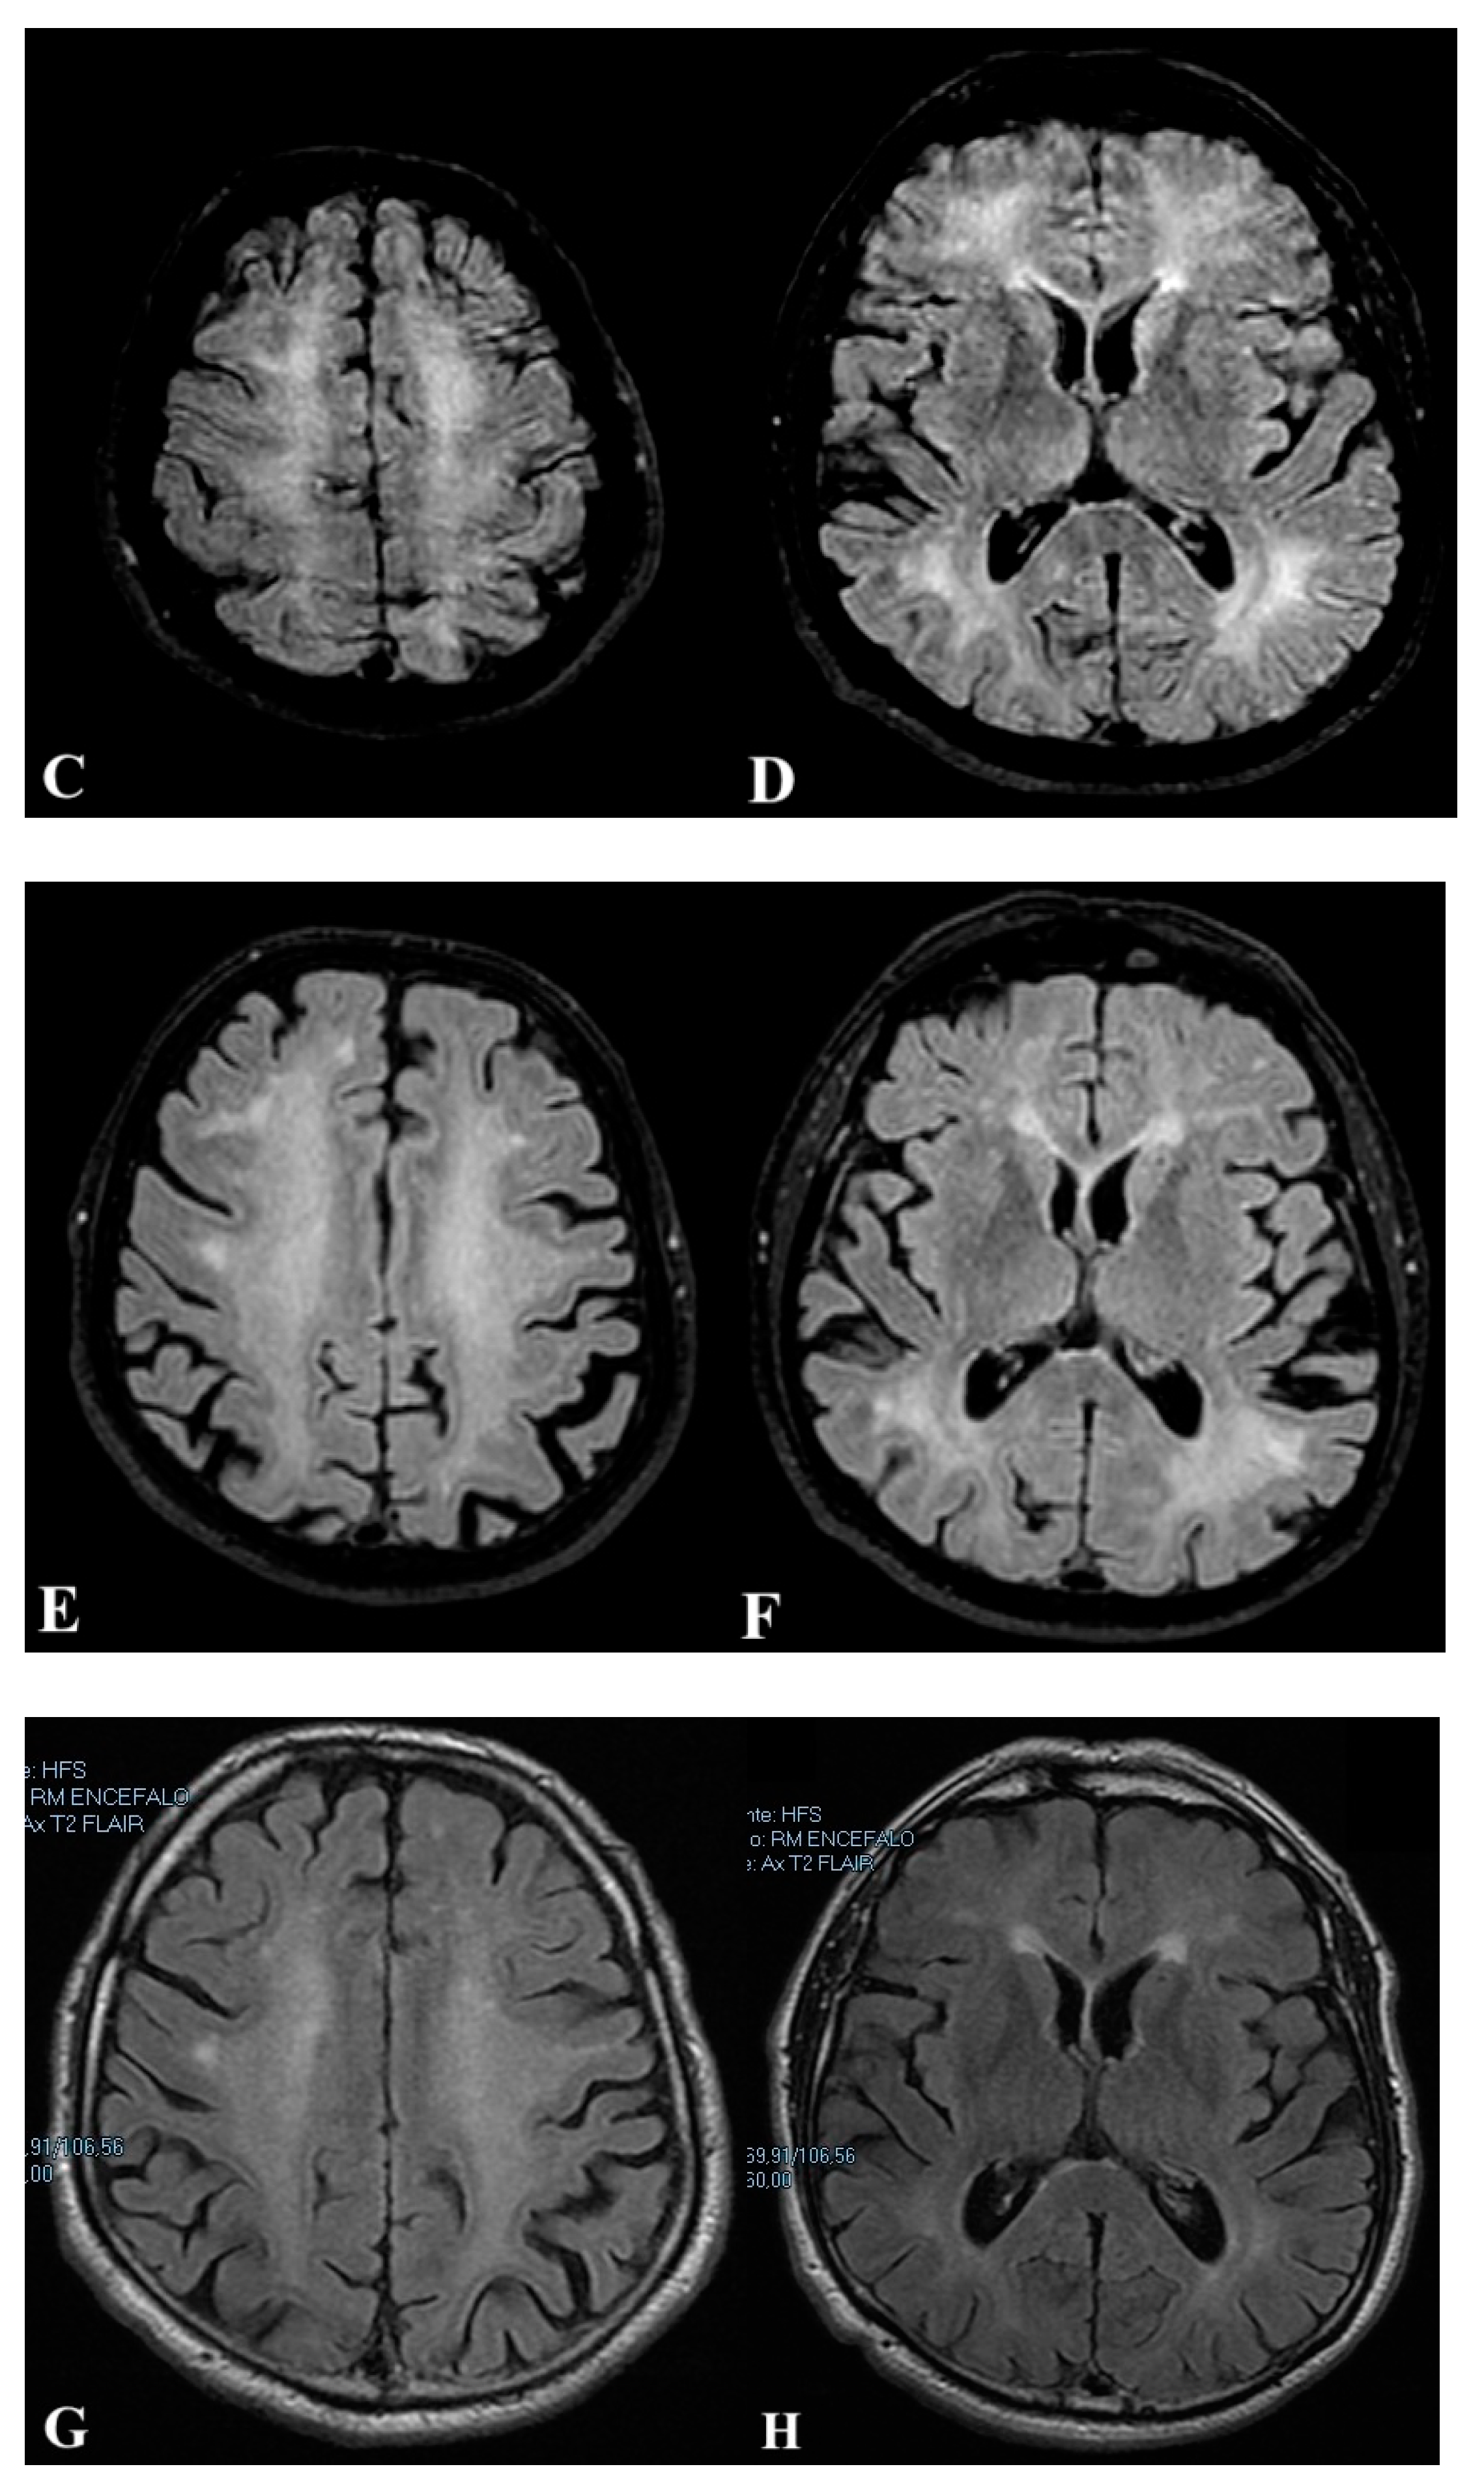

2.1. First Case

2.2. Second Case